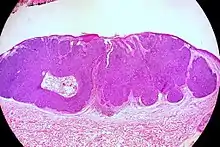

Nodular basal-cell carcinoma

Nodular basal-cell carcinoma (also known as "classic basal-cell carcinoma") accounts for between 50% and 80% of all BCC.[2] It most commonly occurs on the sun-exposed areas of the head and neck.[2] Histopathology shows aggregates of basaloid cells with well-defined borders, showing a peripheral palisading of cells and one or more typical clefts.[17] Such clefts are caused by shrinkage of mucin during tissue fixation and staining.[18] Central necrosis with eosinophilic, granular features may be also present, as well as mucin. The heavy aggregates of mucin determine a cystic structure. Calcification may be also present, especially in long-standing lesions.[17] Mitotic activity is usually not so evident, but a high mitotic rate may be present in more aggressive lesions.[17] Adenoidal BCC can be classified as a variant of NBCC, characterized by basaloid cells with a reticulated configuration extending into the dermis.[17]

Cleft.